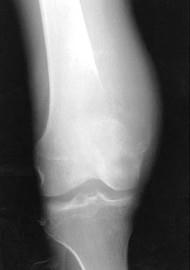

问题 股骨下端肿瘤生长迅速,局部疼痛逐渐加重,有夜间痛,局部皮温增高,关节活动受限,X线检查有骨质破坏和骨膜反应(如图),最可能是 ( )

选项 A、骨肉瘤 B、骨髓瘤 C、软骨瘤 D、骨软骨瘤 E、骨瘤

答案 A